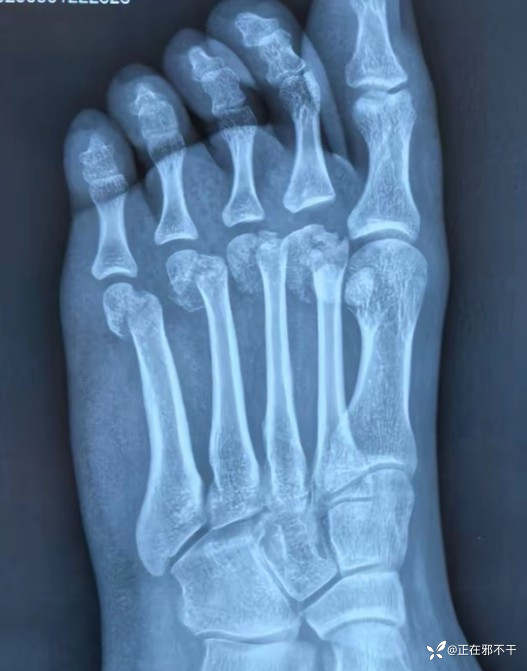

【患者信息】:女,16岁。

【主诉】:骑电动车摔伤之后导致左侧足部疼痛骨折。

【检查】:足部正侧位x光片

左足第二到第五跖骨远端骨折。

【临床诊断】:左足第二到第五跖骨远端骨折